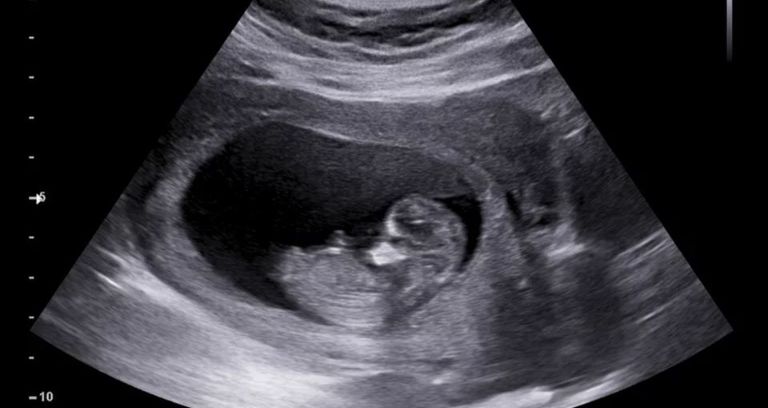

أغلب حالات الحمل البشرية تكون 9 أشهر، وهي تتميز بذلك عن بعض الحيوانات، مثل الفيلة التي يصل فيها الحمل إلى 22 شهرًا.

لكن في بعض الحالات، عندما يموت الجنين مبكرًا، يمكن للطفل أن يبقى داخل جسم الأم إلى أجل غير مسمى.

في بعض حالات الحمل خارج الرحم، الذي يمثل 1-2% من حالات الحمل، يحدث الحمل البطني (بنسبة 1.4%)، أي الحمل الذي يحدث في البطن بدلاً من قناة فالوب أو المبيض.

يمكن أن يفشل الحمل خارج الرحم لعدة أسباب. في كثير من الأحيان، يمكن أن يؤدي نقص إمدادات الدم إلى الجنين إلى وفاته.

إذا مات الجنين قبل الشهر الثالث من الحمل، فإن جسم الأم قادر على تكسير الأنسجة وإعادة امتصاصها، لكن إن كان أكبر لا يستطيع الجسم التعامل معه، فيتم تشكيل حاجز وقائي بينها وبين الجنين، فيحدث التكلس.